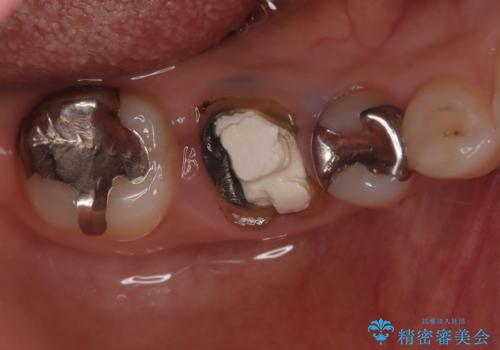

- 右下奥歯が虫歯で被せ物が取れてしまい、また噛めるようにしたいとのことで来院されました。

虫歯が大きく、歯を保存することが難しい状態でしたので、抜歯してインプラント治療を行うこととなりました。